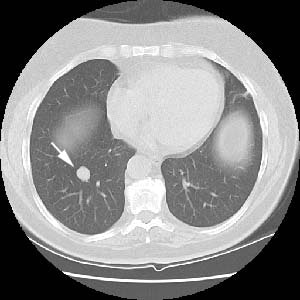

The lesion had well defined margins at CT (white arrow):